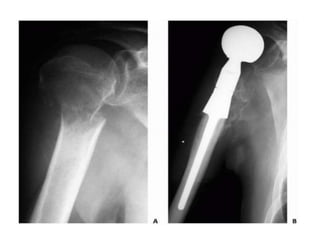

Lobulated partially ill-defined lytic lesion of the proximal Humerus

• Peritrochantric femuris the most likely to cause serious morbidity and therefore threshold for prophylactic intervention is low • Femur account for 65% of pathologic fracture • Humerus and vertebra also require special attention • Mirels scoring system is used to predict the pathological fracture risk. • Clinical prediction of survival is also important which depends on: • Primary site • Number of bone mets. • Involvement of viscera • Haemoglobin level

• Upper Extremity •Scapula, clavicle – non operative • Proximal humerus – prosthesis (long stem), intramedullary nail with multiple screws • Humerus Diaphysis – locked IM nail > plating • Distal humerus – prosthesis, retrograde flexible IM nails > bicondylar plating • Forearm – Rare. IM nails or plating

• Lower Extremity •Acetabular – reconstruction with appropriate prosthesis • Femoral neck – hemi- or THR. Cemented. Long stem • Intertrochanteric – recon nail or prosthesis > DHS • Sub trochanteric – locked IM nail • Femur shaft – locked IM nail preferably cephalo- medullary • Around the knee – locked plating > retrograde nailing